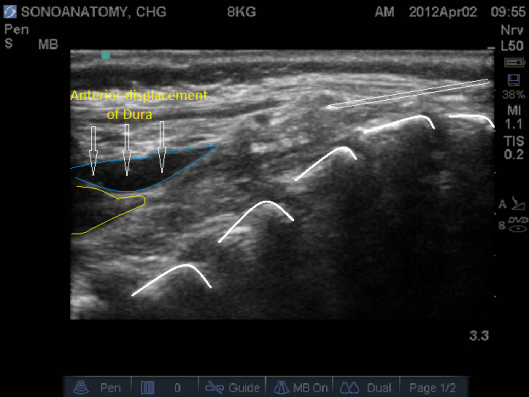

- Inject <0.1ml/kg of normal saline (this avoids wasting valuable LA, and is harmless if injected intravasculalry). See Fig 9 and 10 below. Where the posterior dura can be observed moving anteriorly as the epidural space is expanded.

Fig 10. Ultrasound probe in Midline Longitudinal position, saline test bolus seen as anechoic area displacing the posterior dura anteriorly.

- Correct cannula position will see the test bolus of saline expand the epidural space, displacing the posterior dura anteriorly.